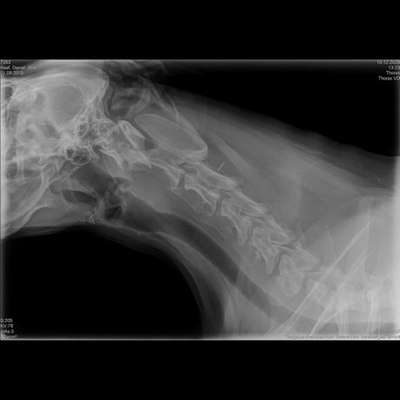

Hallo ihr lieben, Meine 11 Jahre alte Weimaraner Dame hat ca 3-5x pro Tag so eine Art „trockenkotzen“ seit einigen Wochen. Als würde etwas im Hals stecken. An manchen Tagen hat sie es garnicht. Auch beim Knurren oder winseln husträuspert sie sich. Ich habe die Lunge und den Kehlkopf röntgen lassen. Vielleicht kann jemand etwas dazu sagen. Vielen Dank! 🙏

Ich würde jetzt auf den ersten Blick sagen dass das Herz vergrößert aussieht und auch auf dem Brustbein aufliegt aber würde da auch definitiv die Expertise des Tierarztes abfragen

Auf den angefertigten Röntgenbildern lassen sich keine groben Veränderungen der Lunge erkennen, was gut dazu passt, dass die Problematik eher im oberen Atemwegsbereich liegt. Auch ein offensichtlicher Fremdkörper oder eine massive Verlegung der Luftröhre ist nicht zu sehen. Allerdings muss man dazu sagen, dass der Kehlkopf selbst im Röntgen nur sehr eingeschränkt beurteilbar ist. Veränderungen der Schleimhäute, funktionelle Störungen oder eine Kehlkopflähmung lassen sich auf diesen Bildern in der Regel nicht sicher erkennen. Altersbedingte Veränderungen an der Halswirbelsäule sind sichtbar und bei einem Hund dieses Alters nicht ungewöhnlich. Solche knöchernen Veränderungen können indirekt Nerven reizen oder ein dauerhaftes Fremdkörpergefühl im Hals auslösen, erklären die Symptome aber meist nicht vollständig.

Sehr wichtig zu erwähnen ist die sogenannte Kehlkopflähmung (Larynxparalyse). Diese tritt besonders häufig bei älteren, großen Hunderassen auf und zeigt sich genau durch die von dir beschriebenen Anzeichen: Würgen, trockenes Husten, Räuspern, Veränderungen beim Bellen oder Knurren und ein wechselnder Verlauf. Diese Erkrankung ist im Röntgen oft nicht sichtbar und kann nur durch eine Kehlkopfspiegelung unter leichter Sedierung sicher beurteilt werden. Daneben kommen auch eine chronische Entzündung im Kehlkopf- oder Rachenbereich oder ein stiller Reflux in Frage, der ebenfalls zu häufigem Räuspern und Würgen führen kann.

Wichtig ist deshalb, sich nicht allein auf den unauffälligen Röntgenbefund zu verlassen. Der sinnvollste nächste Schritt wäre eine gezielte Untersuchung des Kehlkopfes, idealerweise in einer Tierklinik oder bei einer Tierärztin bzw. einem Tierarzt mit Schwerpunkt Innere Medizin oder Chirurgie. Erst damit lässt sich klären, ob eine Kehlkopflähmung oder eine andere funktionelle Störung vorliegt und wie man deiner Hündin gezielt helfen kann.

Sollten Atemnot, starkes Hecheln in Ruhe, bläuliche Schleimhäute oder eine deutliche Verschlechterung auftreten, wäre das ein Notfall und sollte sofort abgeklärt werden. Insgesamt passen die Symptome sehr gut zu einer Erkrankung der oberen Atemwege, die im Röntgen nicht sicher sichtbar ist.

Der Tierarzt sprach bzgl dem Röntgen von metastasen in der Lunge und entsprechend einem Haupt-Tumor irgendwo und empfahl mir ein Kontrast Mittel MRT.

Ist ist halt die Frage, ob da wirklich metastasen in der Lunge sind. Er sagte zwar, die Schatten auf dem Rö-Bild könnten auch von einer vergangenen Entzündung kommen.. aber sie hatte gesundheitlich seit Baby ab, noch nie eine Krankheit oder irgendwas mit der Lunge…